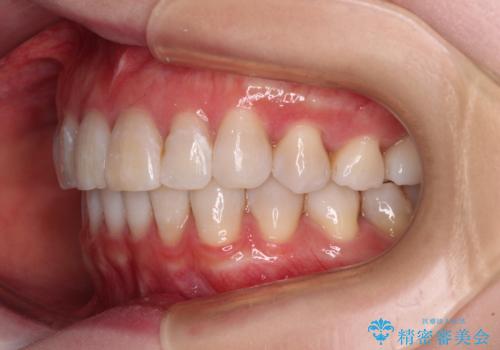

前歯の突出感とデコボコをインビザライン矯正で改善

- 上下前歯の突出感とデコボコを気にして来院された患者様です。

インビザラインによる上下歯列の側方拡大と後方移動、IPR(歯と歯の間を削る)にるスペースの獲得により歯列を整えることとしました。

骨格的な左右差があったため、上下の正中を合わせることができませんでした。

骨格の差は改善できないため、奥歯の咬み合わせに物足りなさを感じましたが、奥歯の咬み合わせによる不自由はなく、口元の突出感も改善することができました。